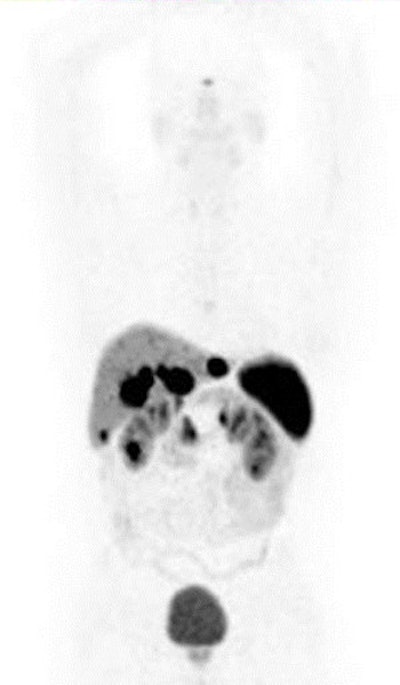

Patient with small-bowel carcinoid shows expression of somatostatin receptors in primary tumor and in liver deposits. The radiotracer Ga-68-DOTA NOC is specific for somatostatic receptors 2, 3, and 5. Maximum intensity projection (MIP) image shows focal uptake in liver and in right upper quadrant (primary tumor in small bowel). All images courtesy of Dr. Ur Metser.

It is also feasible to image receptors and determine receptor density -- a concept that has existed for decades, one common example being somatostatin receptor imaging for neuroendocrine tumors (NETs).

"We know that tumor receptors play an important role in carcinogenesis and tumor growth. Knowledge of receptor expression is key for therapy directed at tumor receptors. We can estimate receptor density with molecular imaging probes," Metser noted. "Our experience has taught us that expression of receptors may be heterogeneous within tumor and even may also vary between primary tumor and metastatic deposits."

Although there are conflicting initial reports, some investigators suggest PET with gallium-68 (Ga-68)-labeled somatostatin analogs may contribute to the early prediction of treatment outcome in patients with well-differentiated NETs undergoing peptide receptor radionuclide treatment. Larger scale trials to clarify the role of PET in assessing response to therapy are pending, he stated.